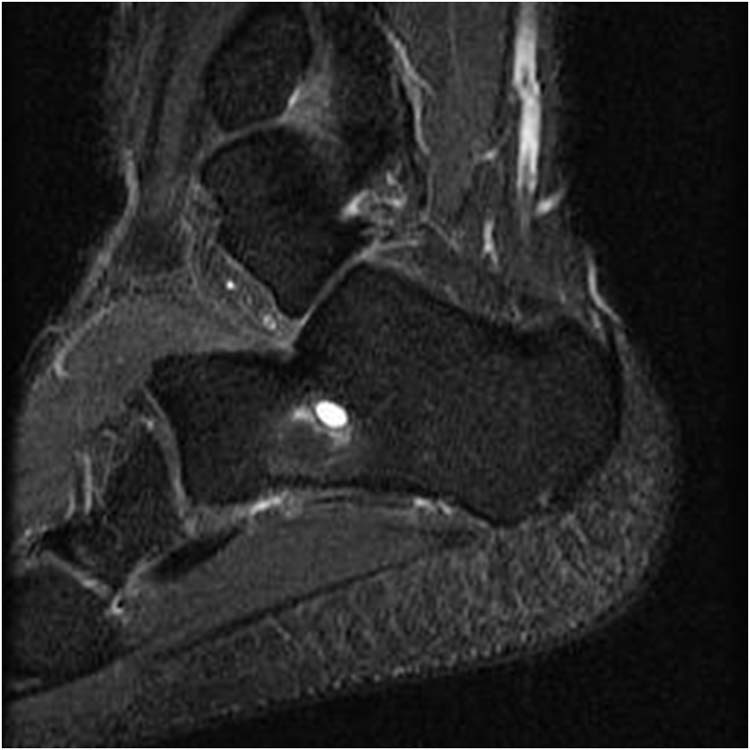

a Coronal view of the ganglion cyst on T2 weighted MRI. b axial view Icing Ganglion Cyst A ganglion is a cyst that typically forms along a tendon in the hand or wrist. Read about causes, symptoms, treatment, and removal (surgery). Sie sind nicht kanzerös, aber sie können schmerzen verursachen, wenn. Ganglionzysten sind mit flüssigkeit gefüllte knoten, die häufig an sehnen oder gelenken auftreten. A ganglion cyst rupture isn’t usually hazardous to your health, but it can. Icing Ganglion Cyst.